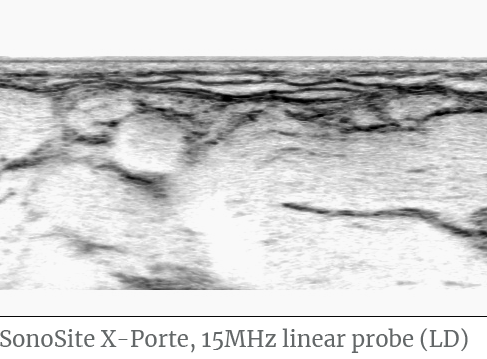

In the wrist crease the nerve lies between the flexor tendons superficially and is recognised by its typical honeycomb structure.

Distal to the wrist crease the nerve descends into the carpal tunnel and runs directly underneath the retinaculum flexorum.